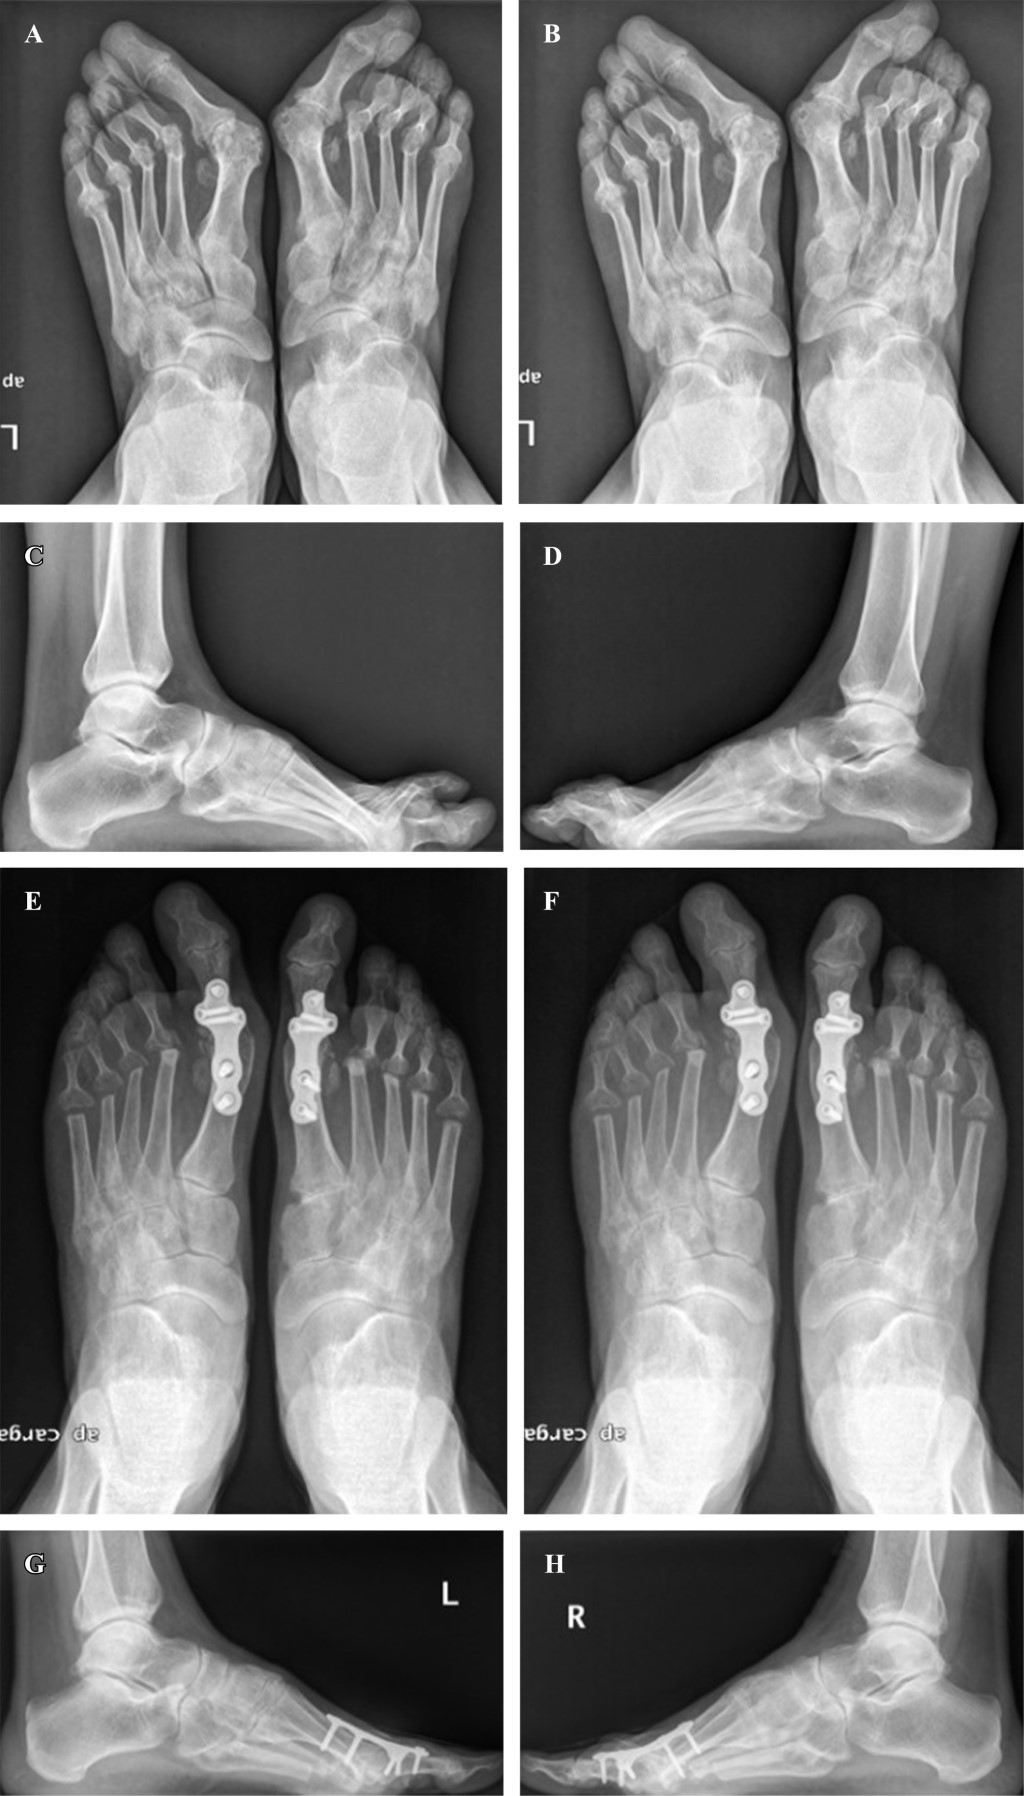

Procedimiento quirúrgico. Todos los pacientes fueron tratados mediante una técnica quirúrgica que consistía en la resección de las cuatro cabezas metatarsales menores a través de una incisión plantar única. La resección se realizó para formar una curva suave con el primer y segundo metatarsiano de similar longitud y la longitud de los otros metatarsianos disminuyendo progresivamente desde el segundo al quinto. Si se indicaba cirugía adicional en la primera articulación MTF, se eligió un abordaje dorsolateral. A este nivel, se realizaron diferentes técnicas que incluyen la fusión de la primera articulación MTF, la artroplastía de resección de la primera articulación MTF o, en algunos casos, ninguna intervención. Se permitió la carga según tolerancia protegida mediante la utilización de un zapato de apoyo en el talón (tacón invertido).

La mayoría de los pies requirieron cirugía adicional en la primera articulación del primer dedo, pero no se efectuaron otras cirugías adicionales inicialmente en los radios menores. Realizamos fusión de la primera articulación MTF en 26 pies (72.2%) y artroplastía de resección de la primera articulación MTF en seis (16.7%). Cuatro pies (11.1%) no requirieron ninguna intervención en este nivel.

Desde el punto de vista radiográfico, el valor promedio del AHV en la última visita de seguimiento fue 21.4 ± 10.6 grados, significativamente más bajo que el valor medio preoperatorio de 49.7 ± 15.2 grados (p = 0.0001). El valor promedio de IMA también mejoró significativamente, desde 14.9 ± 3.6 grados preoperatorios a 8.4 ± 2.5 grados en promedio en la última visita de seguimiento (p = 0.001) (Figura 2).

Antes de la cirugía, tres pies (8.3%) tenían una articulación MTF luxada y 33 (91.7%) tenían dos o más articulaciones MTF de radios menores luxadas. Un total de 25 pies (69.4%) tenían las cuatro articulaciones MTF de radios menores luxadas. En la última visita de seguimiento, seis (16.7%) pies tuvieron recurrencia de la dislocación de la articulación MTF en al menos uno de los dedos menores.

El valor promedio del espacio de artroplastía de resección en el período postoperatorio inmediato fue 4.9, 5.8, 7.4 y 9.8 mm para el segundo, tercer, cuarto y quinto metatarsiano, respectivamente. La suma de todos los espacios de artroplastía de resección en este primer punto de seguimiento fue 27.9 ± 10.3 mm en promedio. En la última visita de seguimiento, estas distancias disminuyeron hasta 1.3, 1.8, 2.5 y 4.4 mm, respectivamente. La suma de todos los espacios de artroplastía de resección en la última visita de seguimiento fue 10.1 ± 7.8 mm en promedio. No se encontraron diferencias significativas entre el espacio de artroplastía de resección y el grado de satisfacción (p = 0.75), ni entre dicho espacio y las puntuaciones en escalas AOFAS (p = 0.17) y MOxFQ (p = 0.11) en la última visita de seguimiento.